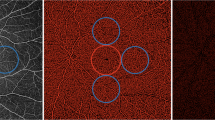

The mean number of arteries localized in the patients were 13.8 (SD = 3.5). The distribution of number of arteries at the posterior pole is shown in Fig. 1.

(a) Cross sectional B scan flattened around the COI that shows entry of short posterior ciliary artery (SPCA) (arrow) (1:1 pixel); (b) En-face scan obtained at the chorio-scleral junction showing entry sites of SPCAs. Dark-black area is the optic nerve location (1:1 pixel); (c) distribution of SPCAs over the posterior pole. Most common location is the center square (each square = 4 × 4 mm2) with a 36% entry site. Second most common is central temporal square (21%) (1:1 pixel).

Total 36% of the arteries were localized at the center of the posterior pole, 7% in the nasal part, 21% in temporal, 10% in the superior square, 11% in the inferior one. Overall, highest number of vessels (more than a third of the arteries) were present in the center of the posterior pole. However, 21% were in the temporal part of the posterior pole. Among the analyzed scans, there were no areas of the scan where the visualization was better which could bias the results.